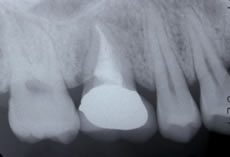

![]() |

治療後のレントゲン。移植歯は安定しています。 |